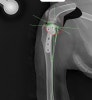

라온동물메디컬센터에서는 TPLO 수술 전정형외과 전용 시뮬레이션 프로그램을 활용해

경골의 각도, 절골 범위, 플레이트 고정 위치를 사전에 정확하게 계산합니다.

​이 과정은 수술의 정확도는 물론, 수술 후 관절 안정성과 회복 속도를 높이는 데 중요한 역할을 합니다.

K는 계획에 따라 우측 TPLO 수술을 성공적으로 진행했습니다.

​수술 후 방사선 사진 / 출처: 라온동물메디컬센터